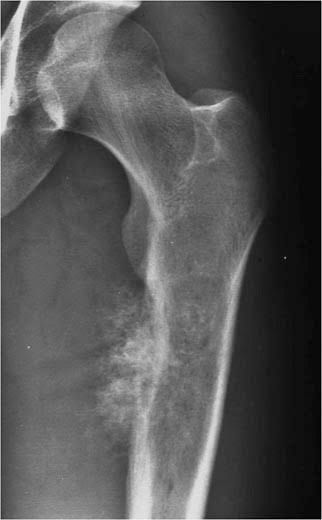

Chondrosarcoma is a type of bone cancer that develops in cartilage cells. Cartilage is the specialized, gristly connective tissue that is present in adults and the tissue from which most bones develop. Cartilage plays an important role in the growth process. What are the symptoms of chondrosarcoma? Large lump (mass) on a bone. Feeling of pressure around the lump. Pain that gets worse over time. Weakness and limited movement in a limb or joint. Local swelling. Joint stiffness. Tumors in the pelvis can cause bowel and/or bladder problems.